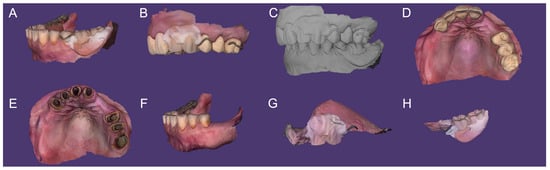

2.6. Optical Impressions and Merging

Intraoral scans (TRIOS 4; 3Shape A/S) of mandibular arch with the relined RPD (Scan A), maxillary arch with FDPs and relined RPD (Scan B), MMR record with prostheses (Scan C), maxillary arch with FDPs (Scan D), maxillary arch without prostheses (Scan E), and mandibular arch without RPD (Scan F) were obtained (Figure 5). Relined maxillary (Scan G) and mandibular (Scan H) RPDs were also scanned extra-orally (Figure 5). And the dynamic occlusion and tooth color were registered.

Figure 5. Digital impressions (TRIOS 4; 3Shape A/S): (A) mandibular arch with prosthesis (relined RPD); (B) maxillary arch with prostheses (FDPs and RPDs relined); (C) maxillomandibular relationship recording (with all dentures); (D) maxillary arch with FDPs; (E) maxillary arch without prosthesis; (F) mandibular arch without prosthesis; (G) maxillary RPD scanning out-of-mouth; and (H) mandibular RPD scanning out-of-mouth.

The aforementioned digital data were uploaded into the CAD software. For the maxillary arch rehabilitation, Scans D and E were merged using palatal landmarks previously described, then superimposed with Scan B and Scan G to create virtual working casts (Figure 6). The same protocol was performed for the mandibular arch. If needed, the scan position was further adjusted manually. The edentulous ridge surfaces were erased on the virtual casts, and the denture-bearing areas were substituted with the relined intaglio of the RPDs (Scans G and H). The working cast thus includes an accurate record of soft tissue displacement and border molding (Figure 6).